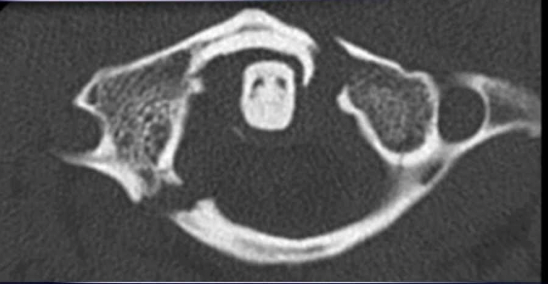

jefferson fx

fx of anterior and posterior arches of C1 caused by severe axial loading (fall on head), best demoed by open mouth views